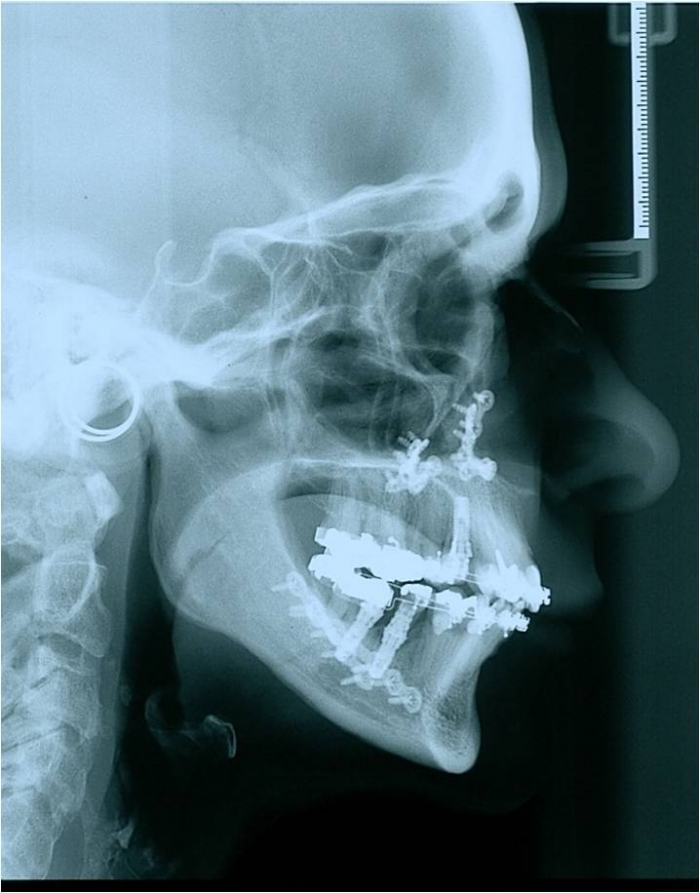

Telerradiografia após a cirurgia